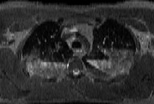

Visible Human male: Sectio transversalis 1358

NMR

Pd T1 T2